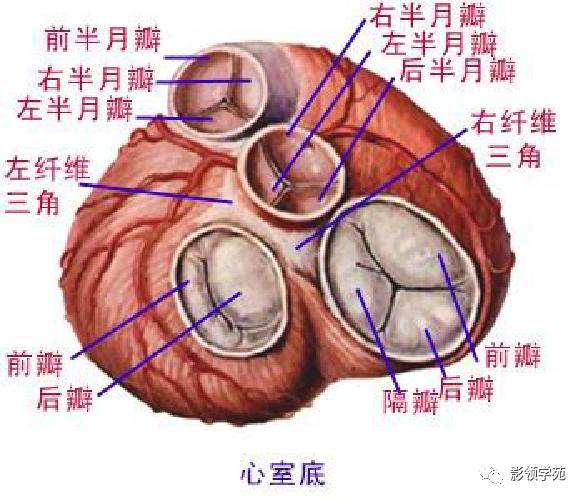

心血管系统

心血管系统